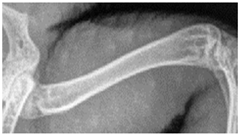

![]() | Right femur: assessability of the trabeculae and cortical bone: etail of the trabeculae and cortical bone, delineability of the structures from the surrounding area. |